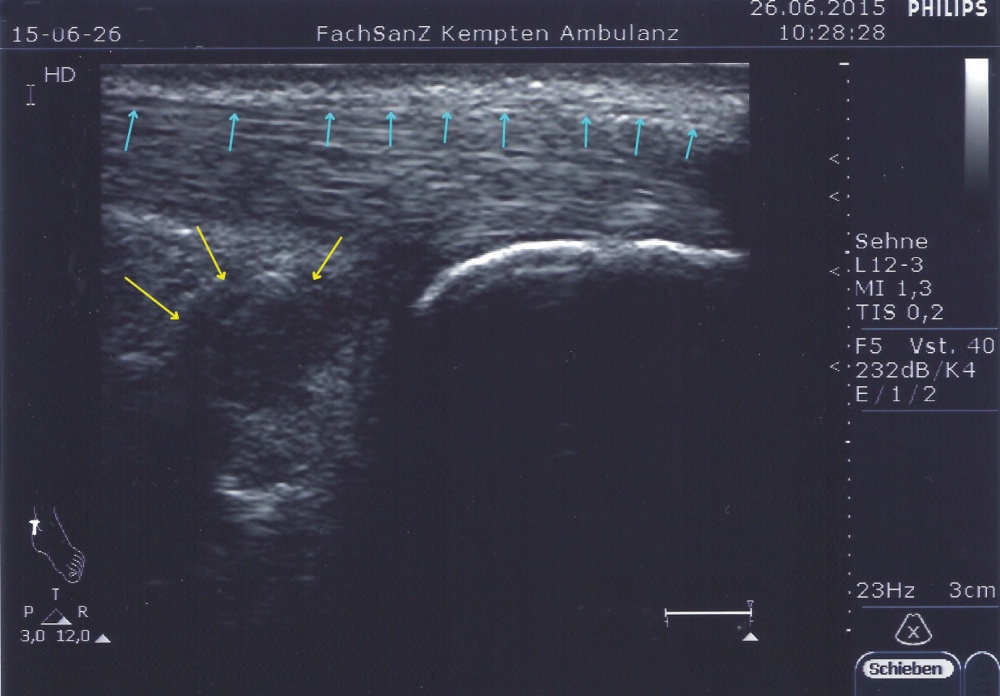

Ein einfacher Test zur Abgrenzung von einer Ruptur der Sehne mit Hämatom, Schwellung und eventuellem Tasten einer Delle ist nach wie vor der Simmonds-Thompson-Test (Plantarflexion des Fußes durch Kompression der Wadenmuskulatur bei intakter Achillessehne). Wie in der Kasuistik beschrieben, erfolgt die weitere Diagnostik mittels Sonographie der Ferse zur Darstellung einer Verdickung, Hypervaskularisation oder Zunahme von echoarmen Arealen. Zudem sollte eine Röntgenuntersuchung durchgeführt werden, um eine mögliche Haglund-Exostose zu detektieren. Eine Kernspintomographie der betroffenen Ferse eignet sich sehr gut zur Darstellung sowohl von strukturellen Veränderungen der Achillessehne, als auch begleitender Entzündungszeichen (siehe Abbildung 3).

Im Rahmen der Diagnostik in der truppenärztlichen Sprechstunde kann neben der obligaten klinischen Untersuchung eine sonographische Darstellung beider Achillessehnen im Seitenvergleich erste Anhalte für die Ursache der Beschwerdesymptomatik liefern.